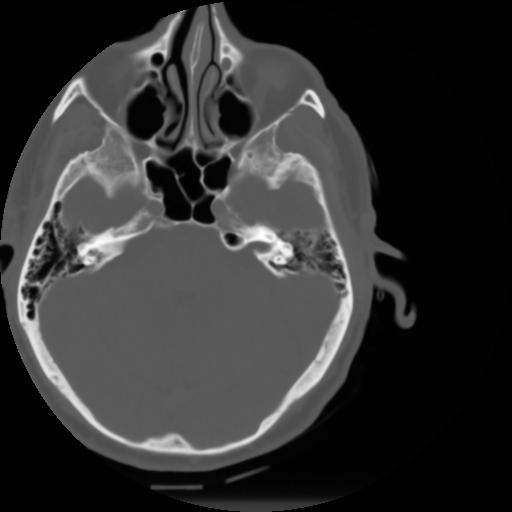

3 CEREBRO,,Axial,3.0,CEREBRO,,